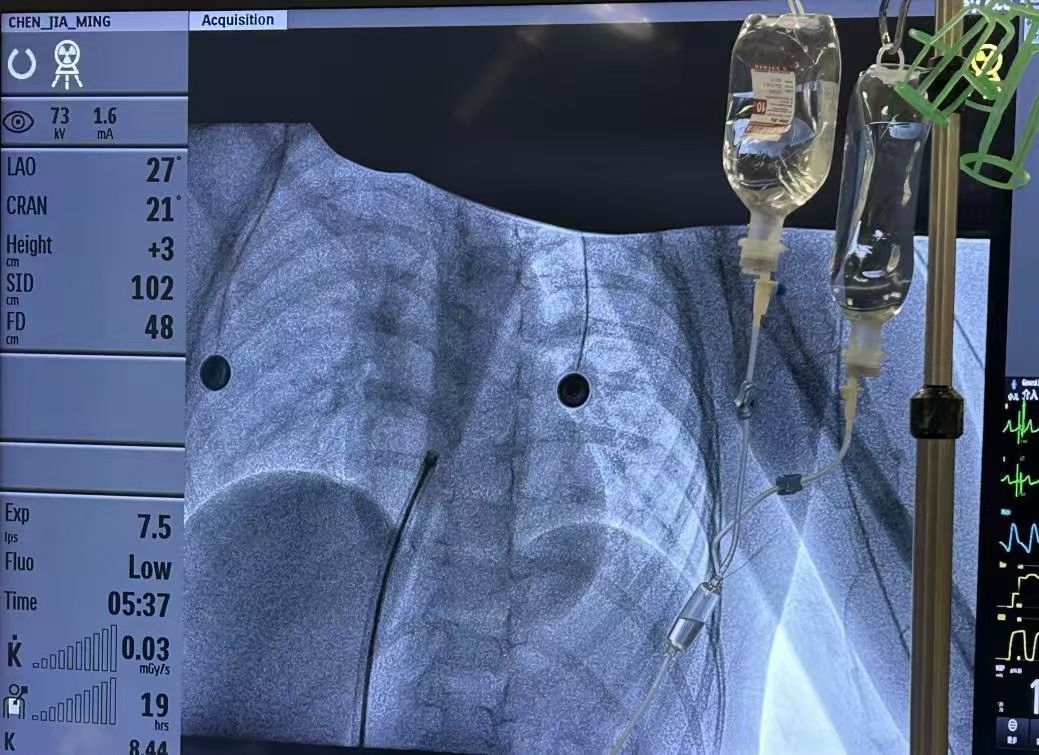

术者团队经股静脉穿刺建立介入路径,在 DSA 及超声双重引导下,将可降解封堵器精准释放至缺损处。

展开后封堵器贴合牢固,术中即刻超声显示分流消失,封堵成功。手术全程仅 40 分钟。 术后患儿无任何不良反应。